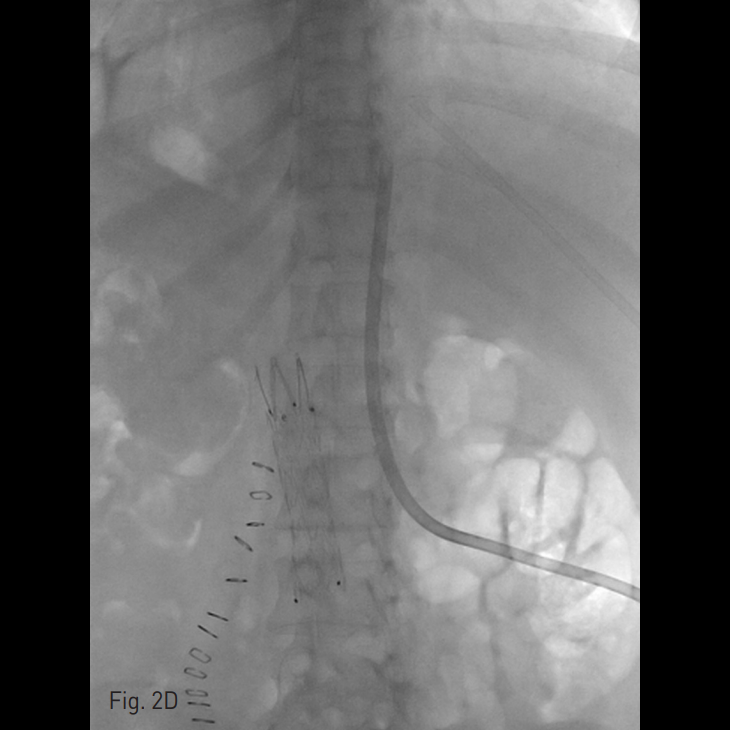

간정맥을 통해 삽입되어 있던 투석용 카테터를 통하여 대정맥으로 풍선카테터를 넣어 풍선을 부풀린 상태에서 이를 표적으로 하여 허리 경유 접근을 통한 투석용 카테터 설치 방법을 계획하였다. 간정맥을 통하여 0.035 inch guide wire를 대정맥 안으로 위치 시키고 9Fr long sheath를 거치한 후 (Fig 2A) guide wire를 통해 16mm-4cm 풍선 카테터 (Boston Scientific, Galway, IRE LAND)를 대정맥 내에 3번 요추 높이 정도에 위치 시켰다. Chiba needle을 이용해 풍선을 겨냥하여 하대정맥을 천자하는데 성공하였다 (Fig 2B). Neff 카테터 (Cook, Bloominton, USA)를 삽입하고 8 Fr, 10 Fr, 12 Fr dilator를 차례로 이용하여 천자 경로를 확장한 후 14.5 Fr, 23 cm Permanent hemodialysis catheter (Conviden, Mansfiled, USA)를 삽입하려 하였으나 저항이 심해 대정맥 내강 안으로 충분히 진입하지 못하였다 (Fig. 2C). 이에 guide wire를 140cm stiff guide wire로 바꾸고 permanent hemodialysis catheter의 sheath의 끝을 구부린 후 심장 쪽으로 최대한 밀어 넣어 성공적으로 카테터를 삽입할 수 있었다 (Fig. 2D).

Fig. 2. Successful placement of translumbar tunneled dialysis catheter.

D. Finally the tunneled hemodialysis catheter could be inserted with the tip at the entrance of the right atrium.